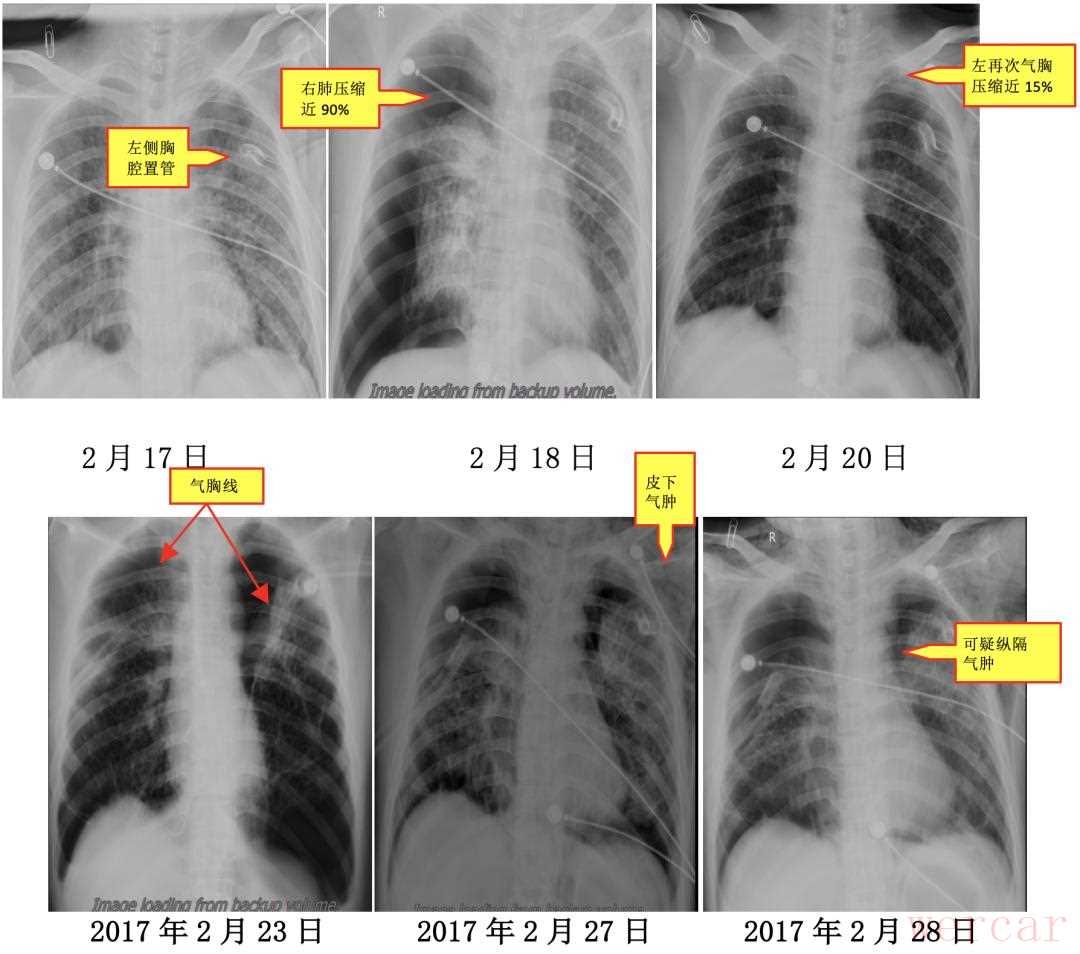

由于该患者病情进展迅速,双肺组织破坏严重,现有的治疗方法疗效均不确切,家属拒绝了肺穿或肺活检进一步确诊,同意于2017年2月14日开始口服强的松30mgQD,并给予抑酸、补钾及保护胃黏膜治疗。患者于2017年2月17日中午,突然出现胸闷、气短、呼吸困难、大汗淋漓,指脉氧饱和度下降至74%,左肺叩诊呈鼓音,听诊左肺呼吸音消失。考虑左侧气胸,行左侧胸腔置管,先后抽出6300ml气体,指脉氧饱和度升至83%,仍可轻松抽出气体。后行左侧胸腔闭式引流术,指脉氧饱和度升至90%,患者气短好转。

第二日(2月18日)凌晨1点30分,患者饮水呛咳后,再次出现呼吸困难,血氧饱和度下降,复查床头胸部正位片(2月18日)示左肺已复张,但右肺压缩近90%。立即行右侧胸腔闭式引流术。随后,患者出现发热,痰培养出现敏感鲍曼不动杆菌。给予敏感抗生素治疗,体温渐降。但闭式引流不能使肺复张,患者仍诉气短呼吸困难,复查床头胸部正位片(2017年2月23日)示右肺未完全复张,左肺再次被压缩近15%。遂给予床头负压吸引,但效果仍不佳。吸氧5升/分,复查动脉血气示(2017年2月24日)PH 7.365,PCO2 53.4mmHg,PO2 60.6mmHg,SaO2 89.3%,BE 3.3mmol/l。颈部和前胸部触及皮下捻发感,复查床头胸部正位片示双侧气胸,引流管内一直有气泡涌出,可能形成了交通性气胸和/或不断有肺泡破裂,导致无法拔除闭式引流管。多次请胸外科会诊,可否行胸膜修补术或胸膜固定术?但胸外科医师分析患者胸部CT,认为肺组织严重弥漫性破坏,胸腔镜下胸膜修补或固定术难以实施。患者疾病进展迅速,2017年2月28日复查床头胸部正位片示双侧气胸,皮下气肿,可疑纵隔气肿。最终,家属决定转回当地医院治疗。 尽管LCH是一种罕见病,但其在早期也有一些蛛丝马迹,如多饮多尿,CT片上的多发囊状影及小结节、垂体形态的改变、尿比重下降等。如能早期识别,预后可能完全不同。遗憾的是这例患者诊断时已属晚期,肺组织严重破坏,又缺乏有效的治疗方法,加之疾病进展快,预后不佳。